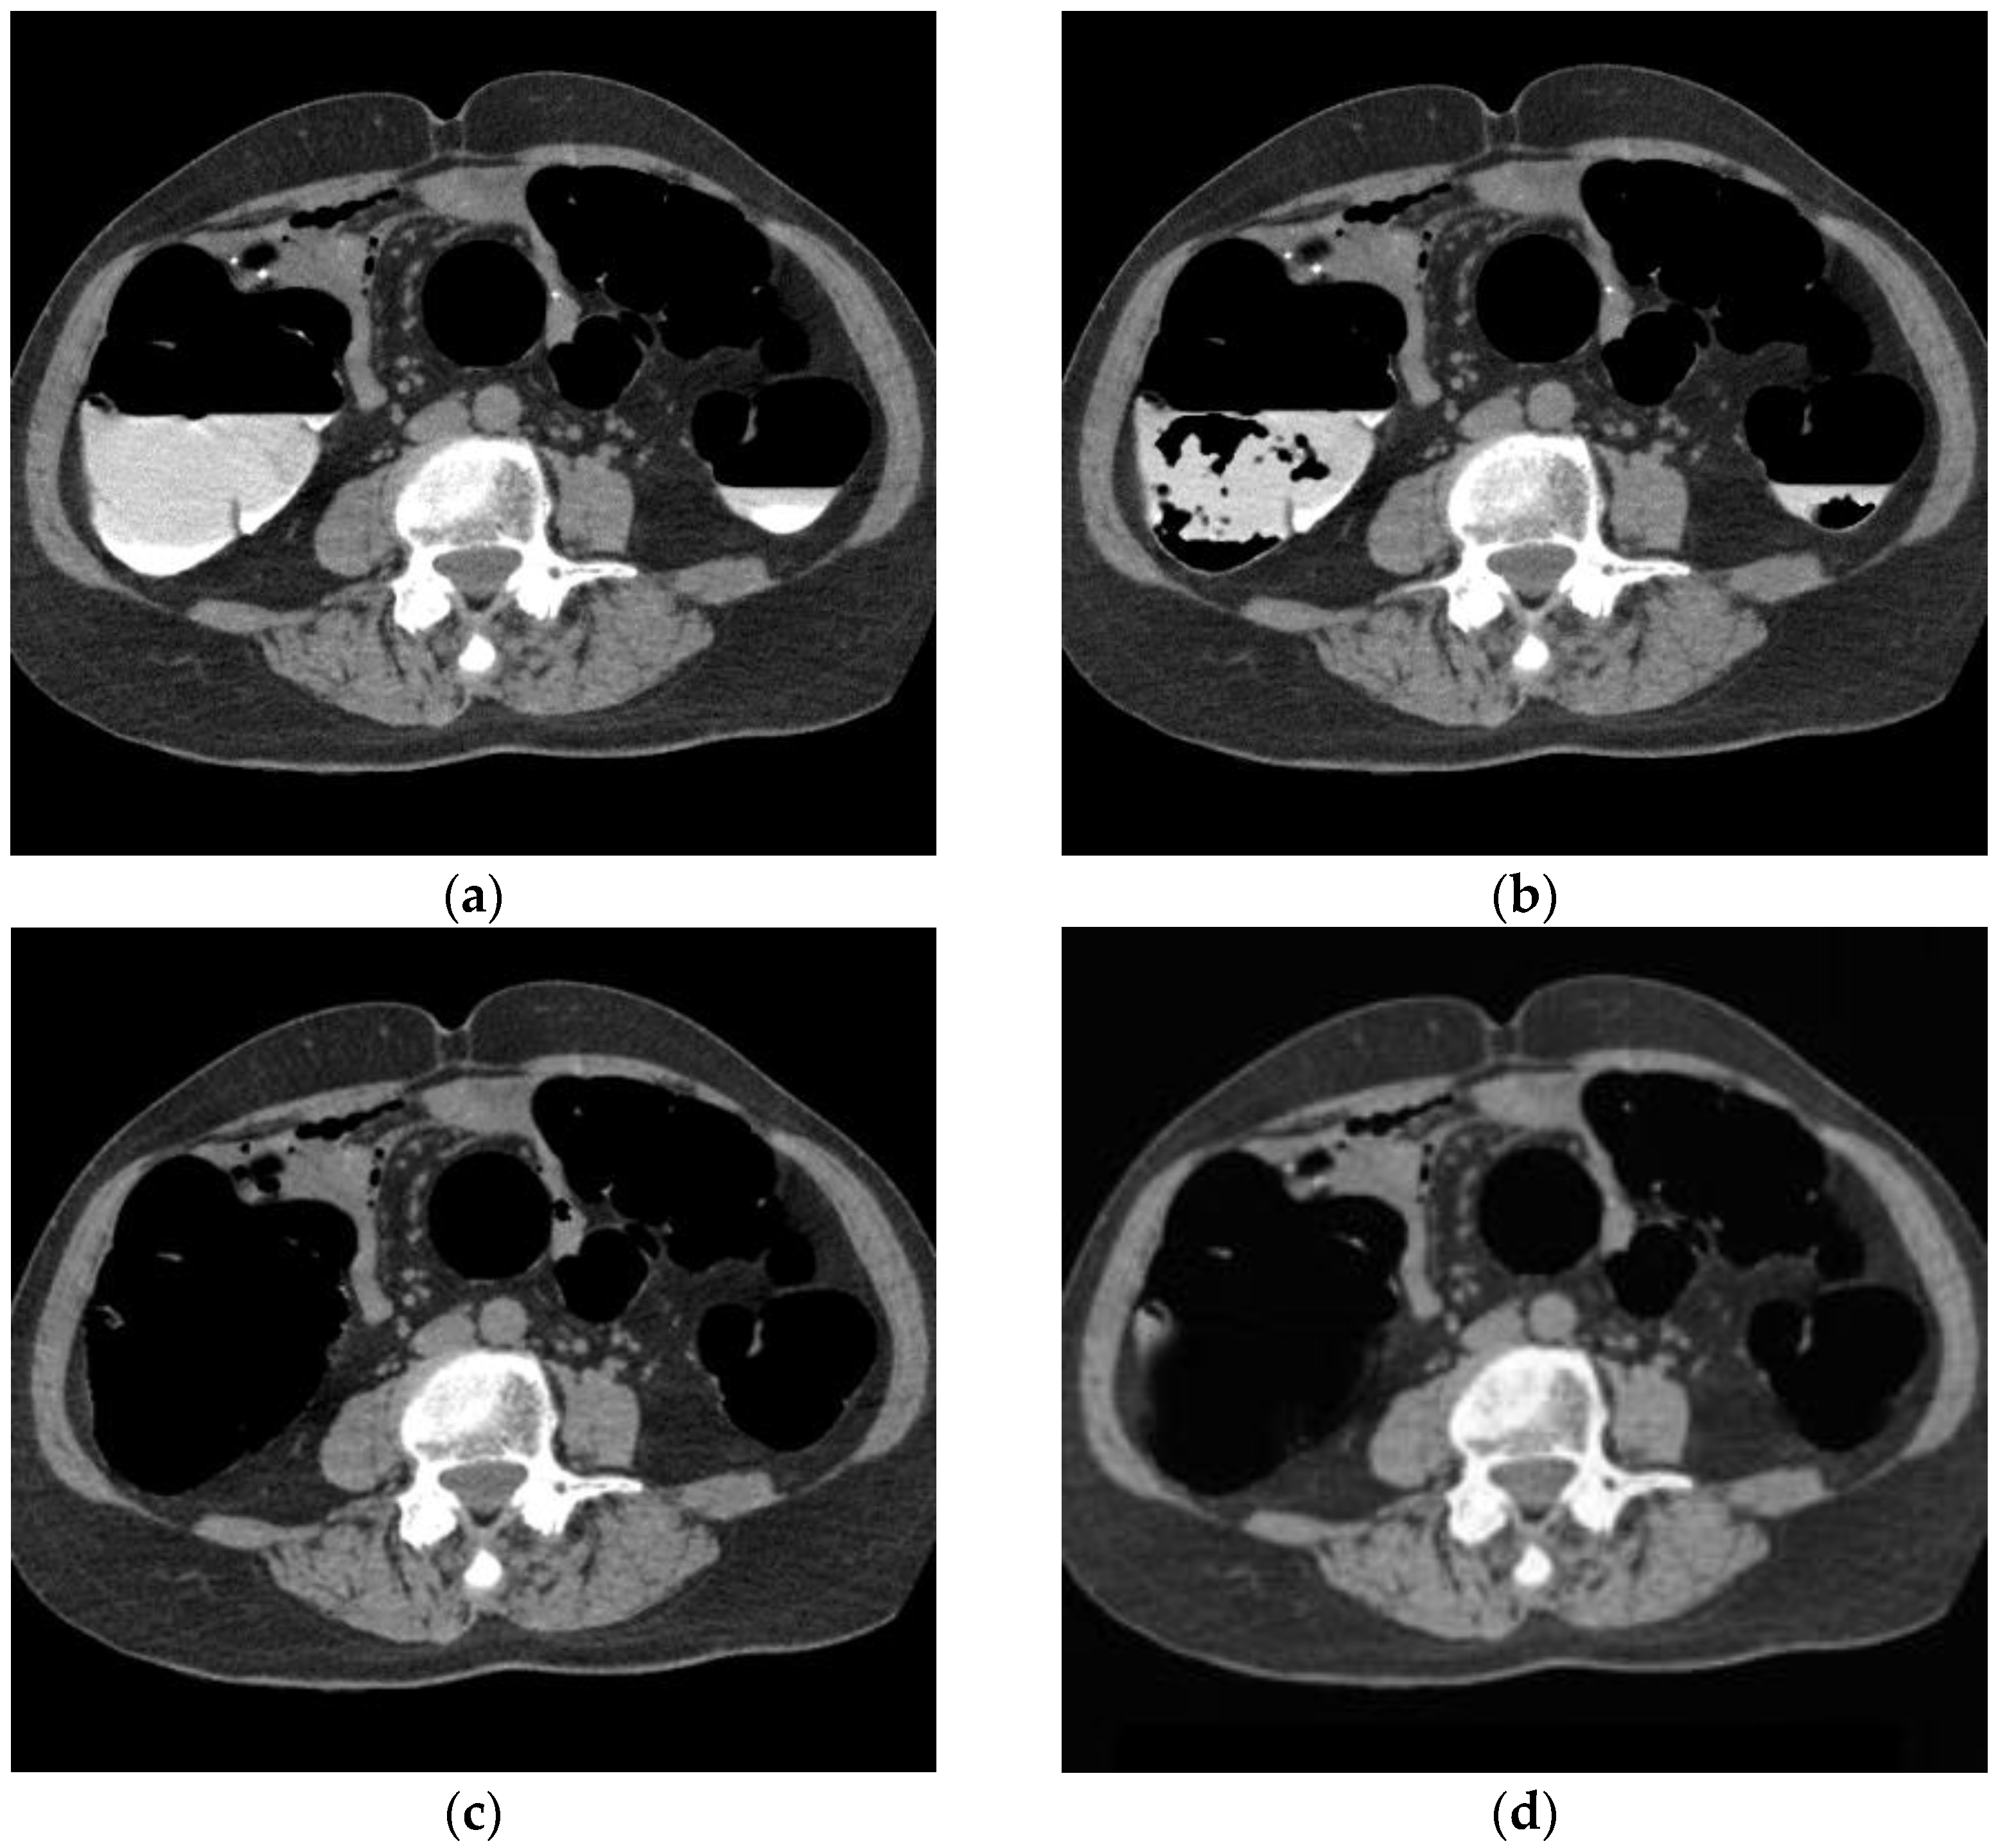

Figure 9 shows the results of applying the proposed method to images of the lesions. Both the conventional and proposed methods extracted rectal polyps of 13 mm and 9 mm in diameter, early stage cancer of the rectum, and perirectal lymph nodes without any loss of morphology due to processing. As shown in Figure 9, aortic calcification and renal calculus, which have high CT values similar to barium, were not removed from the images of the colorectal lesions. In addition, mass lesions of the liver and fatty liver lesions with low CT values were also depicted.

Figure 9.

Cleansing image of the proposed method of the lesion. (Left: MC image and Right: cleansed image using the proposed method.) (a) Rectal polyp; (b) early rectal cancer; (c) kidney stone; (d) petrification of aorta; (e) mass lesion of the liver; and (f) fatty liver.